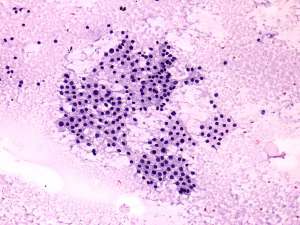

Cytology was performed from the right thyroid. Cytological diagnosis: benign pattern corresponding to hyperthyroidism.TSAb proved to be minimally elevated 2.4 U/mL (normal value below 1.5).